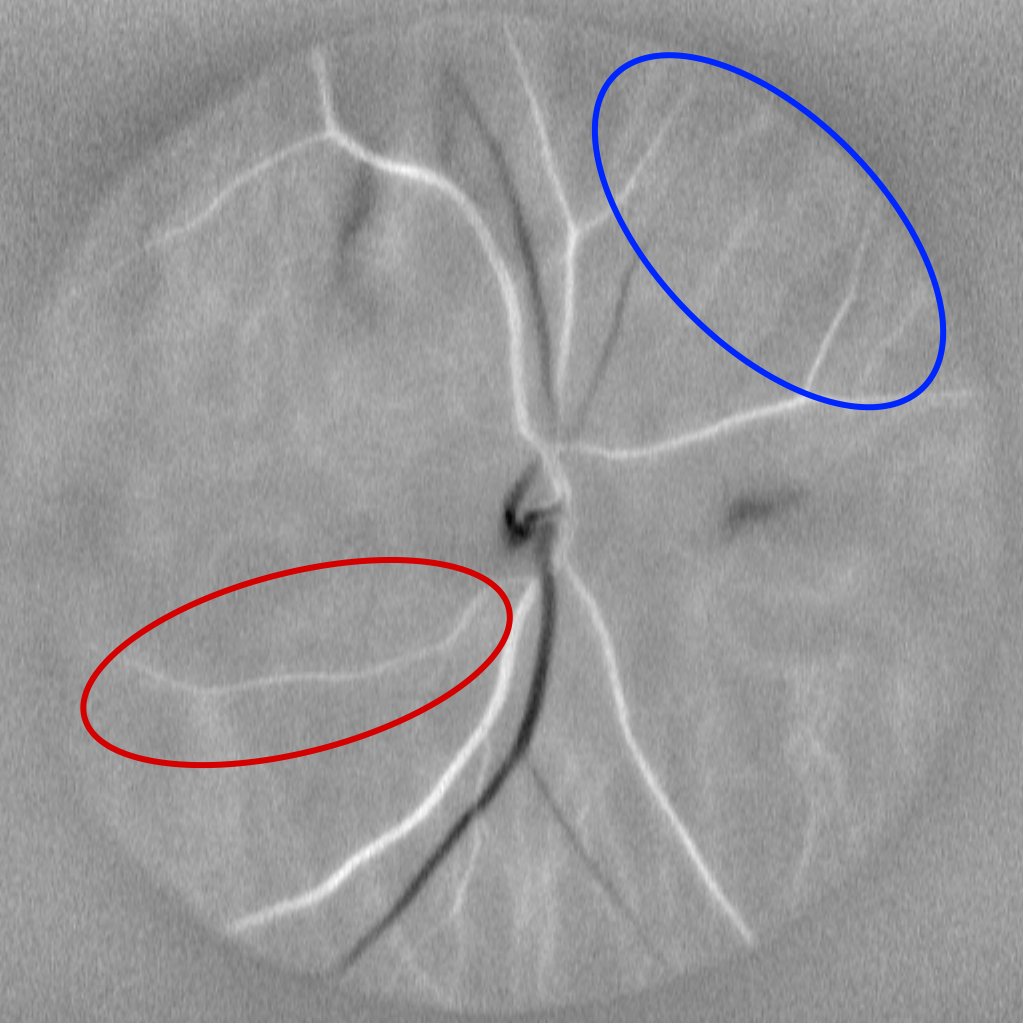

(c) Diasys image

Fig. 1: Different processing of the M0 video. Its average M0 image (a) looses temporal fluctuations, but offers better visualization of the vasculature, including choroidal vessels, not connected to the centered optic disc. Correlation map (b) and Diasys image (c) both convey retinal hemodynamic information, but they respectively better reveal arteries and veins, as shown by red (artery) and blue (vein) selections.

The Doppler Power Spectrum Density (DPSD) is obtained by computing the squared magnitude of the filtered Fourier spectrum for each time window. The moment of order zero of this spectrum (denoted M0), obtained by integrating the DPSD over all frames, enables the visualization of blood flow dynamics across the cardiac cycle. It is the data used throughout our pipeline. The accumulation of each frame produces Power Doppler images - M0 images (see figure 1) - providing a high-resolution map of the retinal vasculature, but losing its temporal fluctuations.

• Finally, artery–vein segmentation is performed by providing the Power Doppler image, the correlation map, and the diasys image (defined as the systolic frame minus the diastolic frame) as inputs to the model. The diasys image and the correlation map convey similar information, but they differ and can be complementary, as shown in fig 1. Table 2 shows their impact on training.